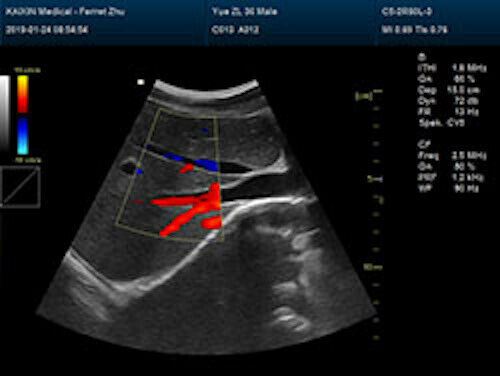

Large Animal Veterinary Color Doppler Ultrasound & Rectal Probe

| Powerful function & Configuration • Large screen display • Built-in lithium battery • Small size, light weight, easy to carry, N.W. ≤ 5kg • Equipped with a wide range of probes for abdominal, obstetric, vascular, cardiac, small organ, urinary applications • Built-in 4D module with optional 4D volume probe • A variety of digital peripheral interfaces, provides a variety of image output methods • PC platform, easy to operate, meet various software upgrades |

| Rich clinical application function • B+CF (Dual Images) • B+CF/PDI/DPDI+PW (Triplex) • Convex extended imaging technology • Linear array deflection/Trapezoidal imaging technology • Spatial compound Imaging technology • Panoramic imaging technology (optional) • 3D/4D imaging technology (optional) • Speckle noise removal technology • Pulse inversion tissue harmonic imaging technology (iTHI) |